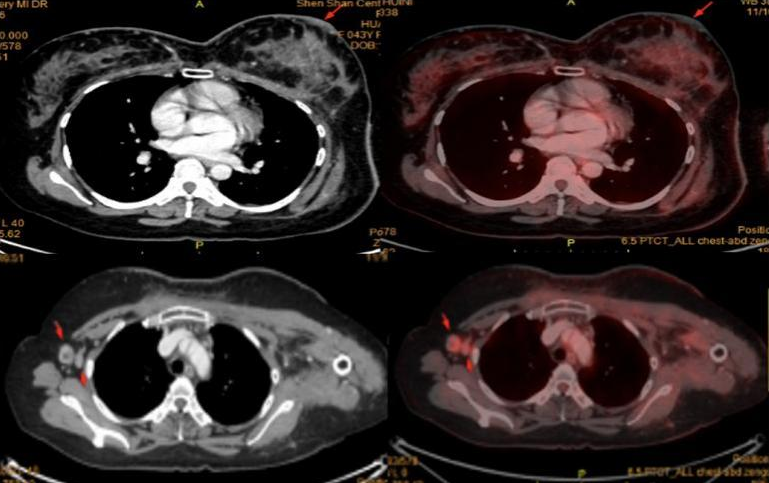

胸部CT:双侧斜裂及右肺下叶新发实性结节,较大约4mm×4mm,建议随诊复查。

PET-CT:考虑左乳皮皮肤转移伴炎症可能;右侧腋窝淋巴结转移。余未见明显异常。

6程后复查乳腺MR、胸部+上腹部CT、乳腺彩超,提示:左乳病灶范围较前明显缩小,右腋窝肿大淋巴结消失。